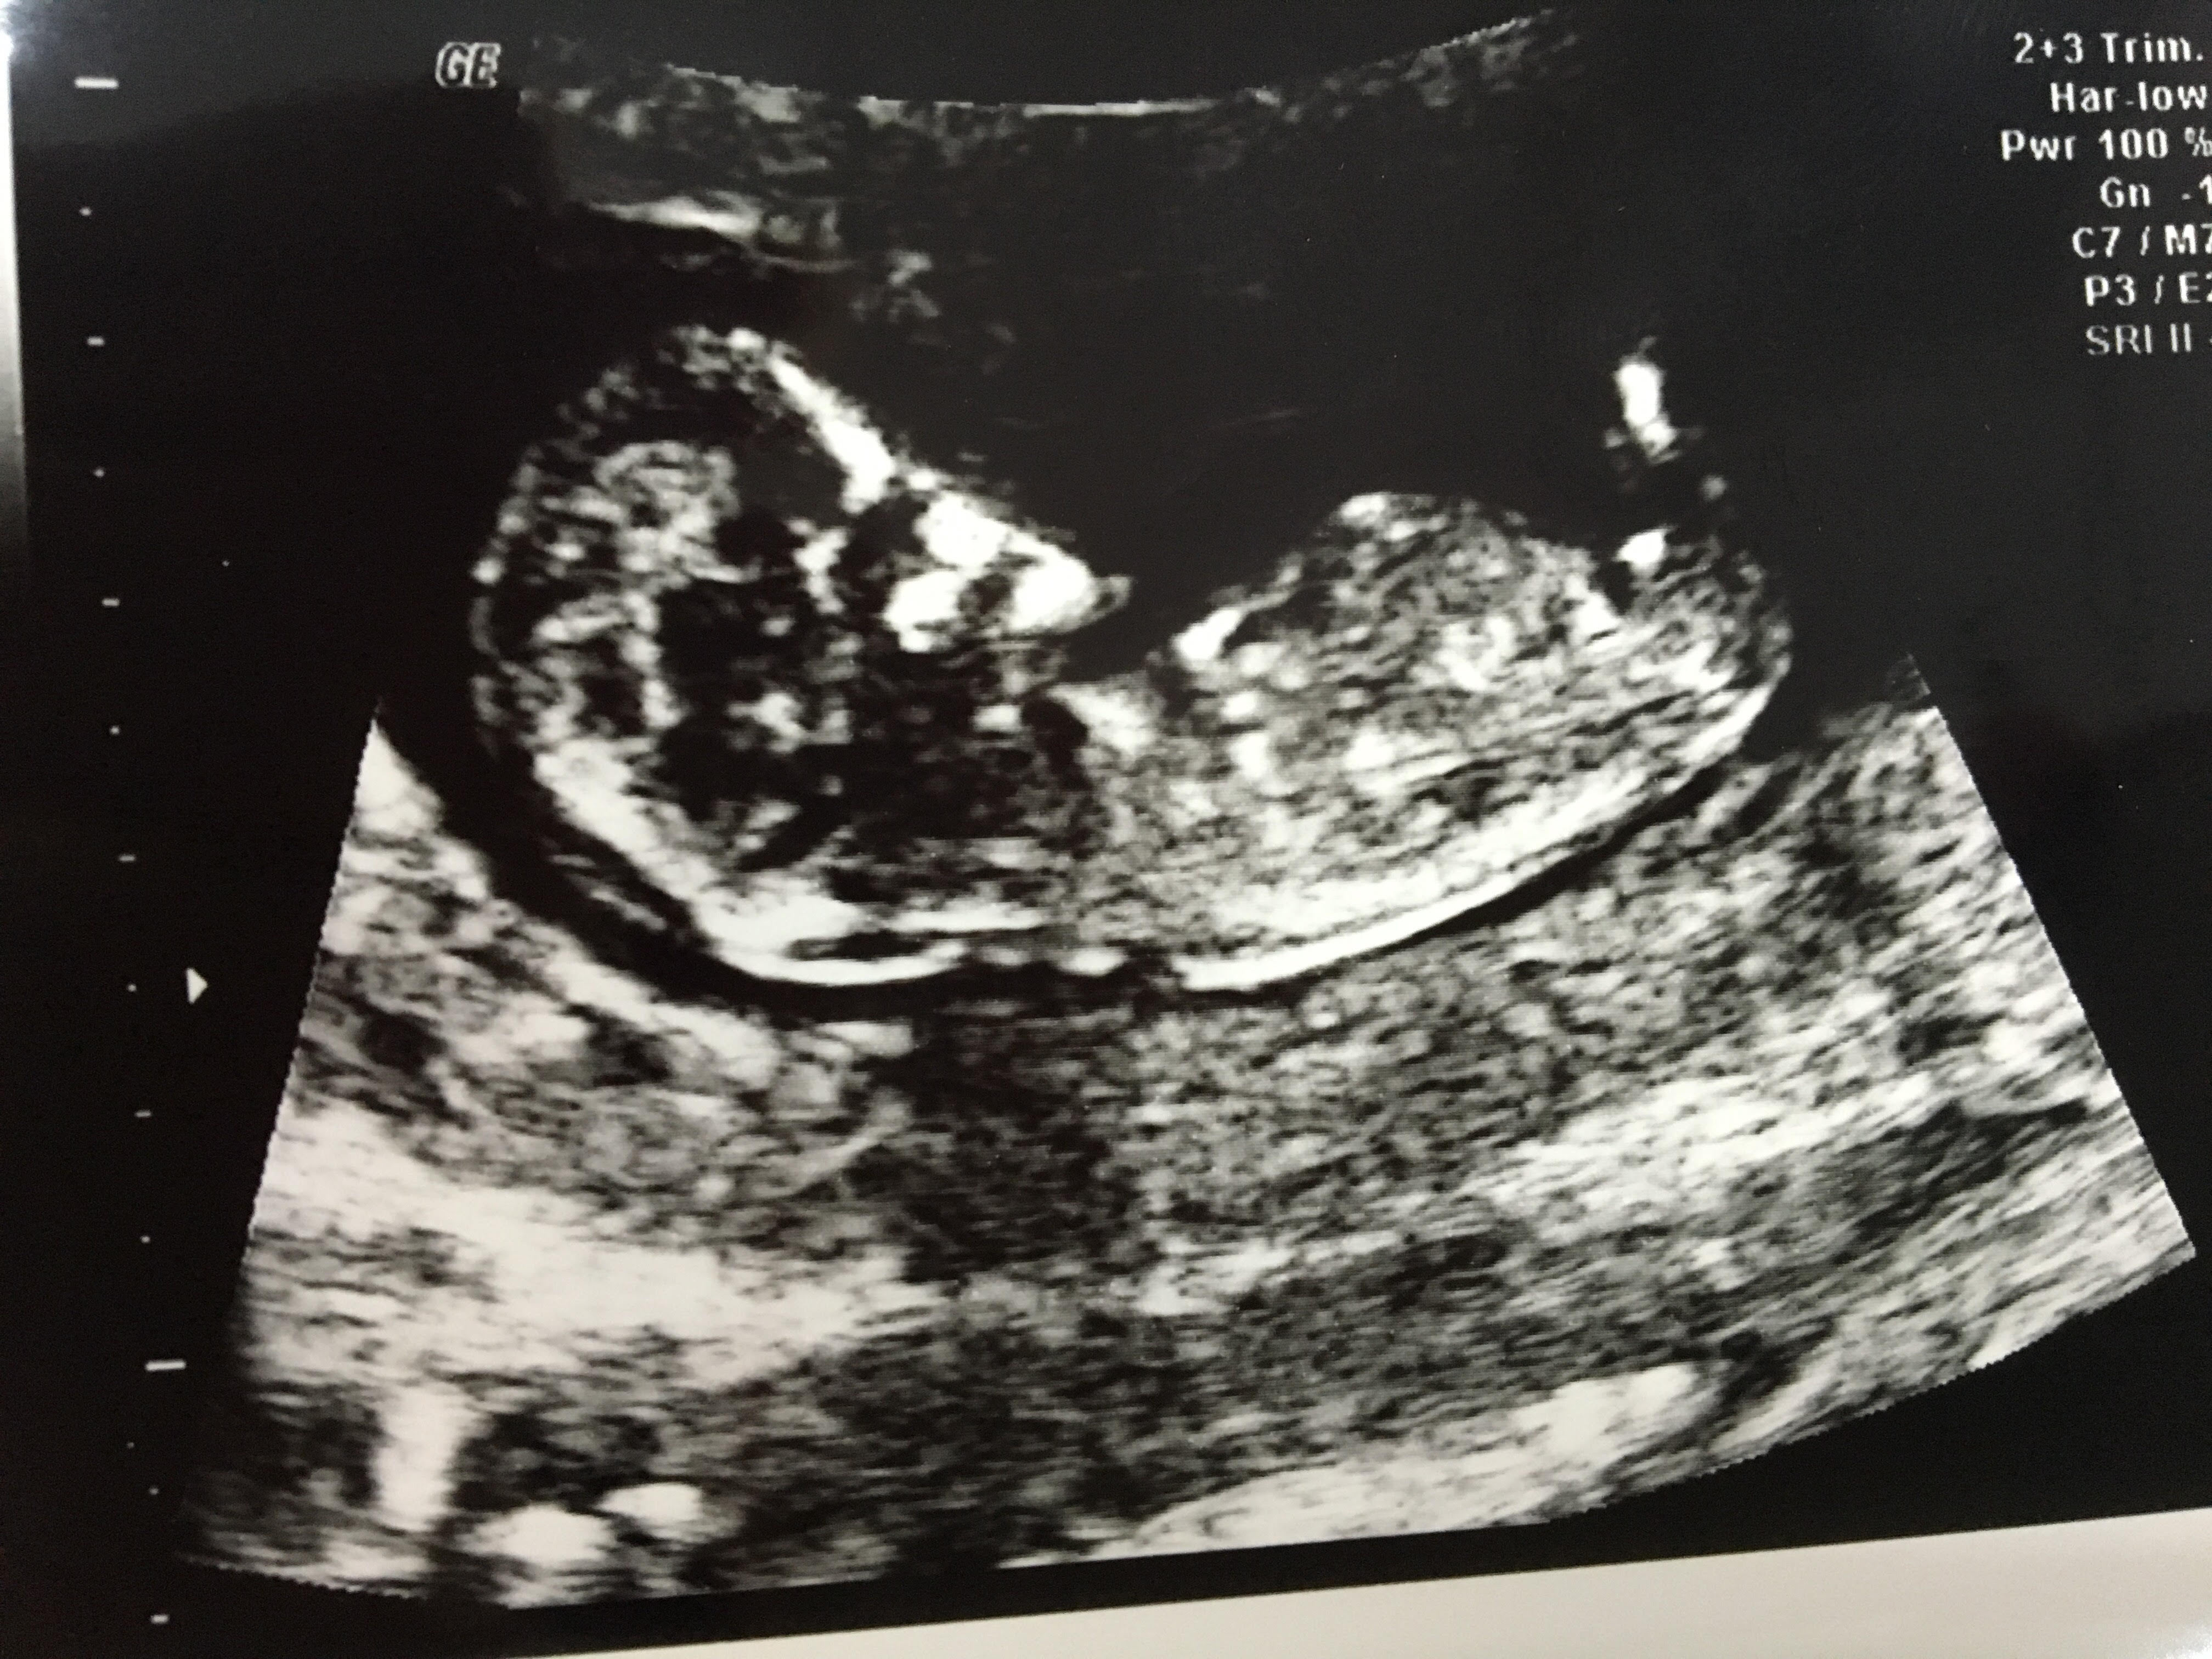

M melek112 Yeni Üye Üye 9 Ocak 2017 #124 Bunu da yorumlar mısınız Ekli dosyalar image.jpeg 875,5 KB · Görüntüleme: 713